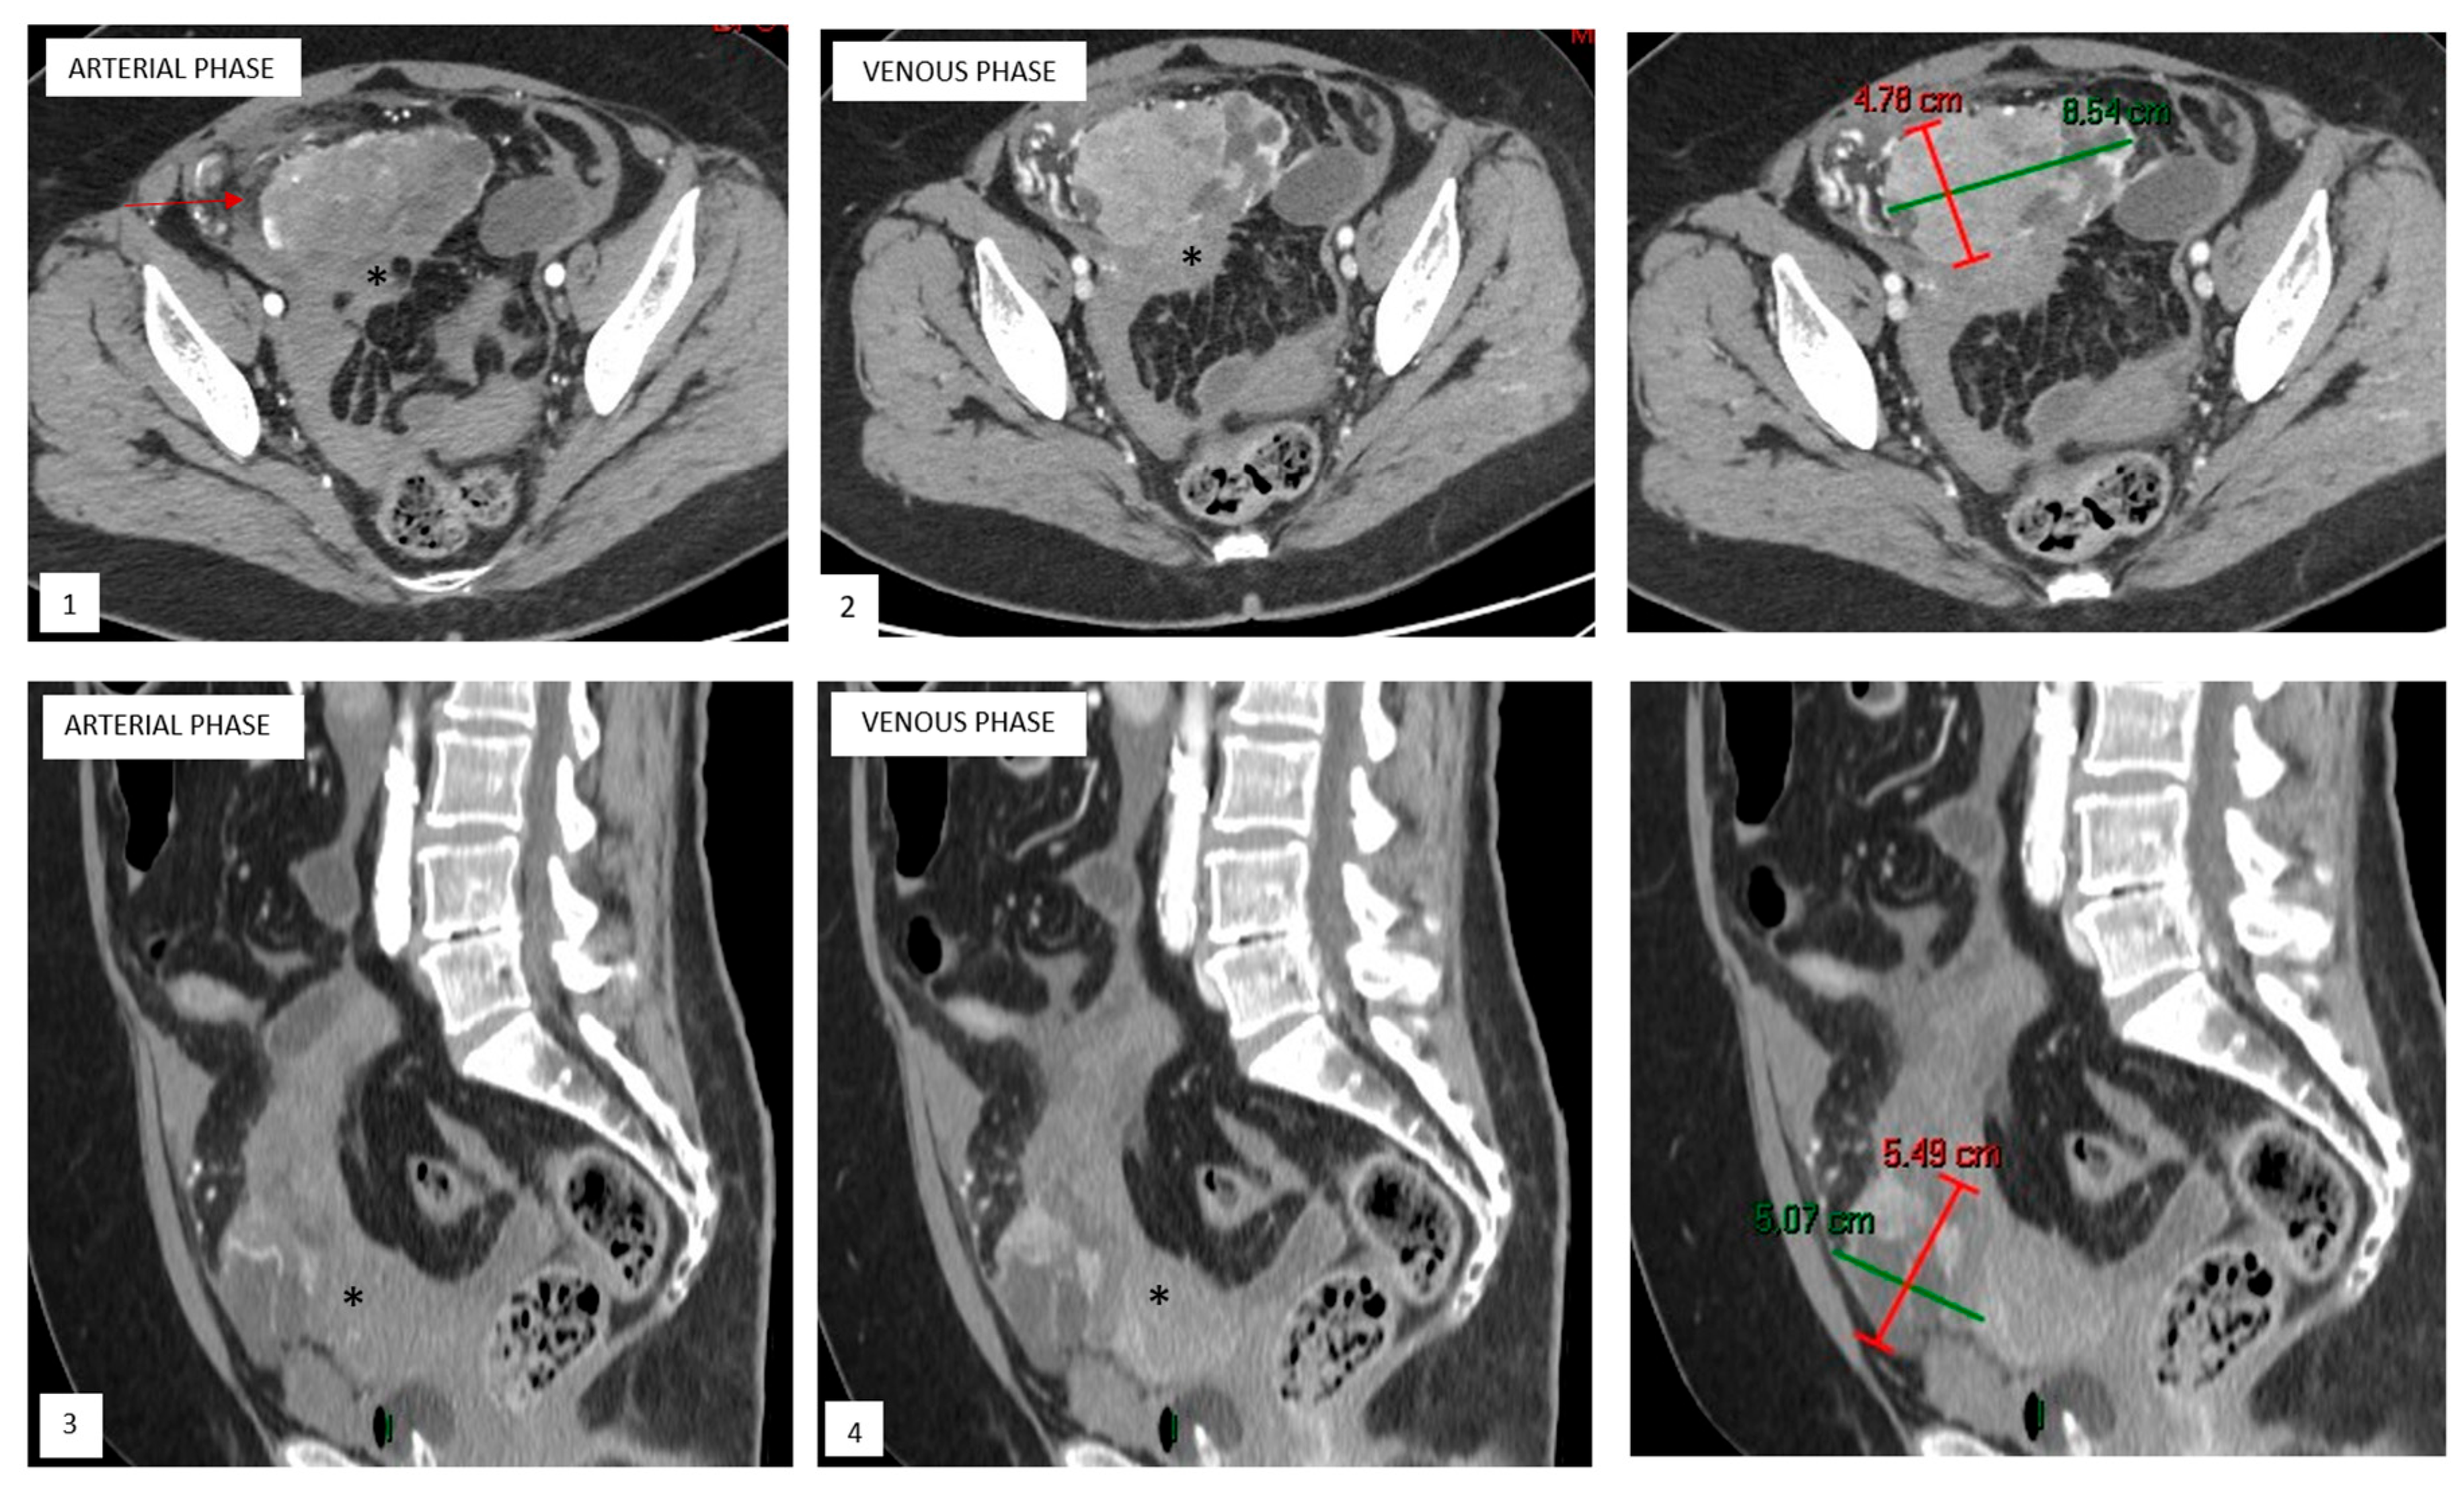

Upon computed tomography (CT) (Figure 1), uterine PEComas typically appear as iso- to hypodense masses relative to the surrounding myometrium on non-contrast images. Additionally, internal hemorrhage can be seen as hyperdense areas [16,22].

Figure 1.

Axial and sagittal reformatted contrast-enhanced CT pelvic image of ruptured uterine PEComa with hemoperitoneum. Axial and sagittal reformatted contrast-enhanced CT pelvic images reveal a well-marginated mass arising exophytically from the uterine fundus (*), with hypoattenuating areas consistent with cystic/necrotic changes and solid components showing progressive heterogeneous enhancement during arterial ((1,3)) and venous ((2,4)) phases. A small amount of peritoneal fluid can also be noted (arrow).

Magnetic resonance imaging (MRI) is also nonspecific. On T1-weighted sequences, these tumors typically show hypo- to isointensity compared to skeletal muscle. The areas of hyperintensity may indicate hemorrhage or fat. On T2-weighted sequences, PEComas tend to be hyperintense, likely due to the presence of cystic or necrotic areas within the tumor [16,17,21,22]. Fat suppression sequences can help identify intratumoral fat. Restricted diffusion may be present in malignant PEComas. Post-contrast CT and MRI images demonstrate heterogeneous and pronounced enhancement, reflecting their rich vascular supply [16,17,21,22].